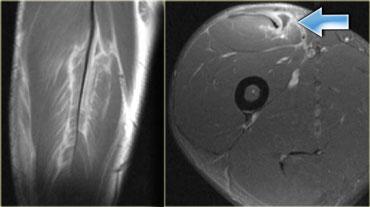

Hình ảnh bên trái minh họa rõ nét sự sắp xếp dạng lông vũ của chỗ nối cơ-gân trong một cơ bị teo.

Hình ảnh bên trái cho thấy phù nề xung quanh chỗ nối cơ-gân theo dạng hình lông vũ.

Đây là hình ảnh rách hoàn toàn cơ thẳng đùi (mũi tên).

Cấu trúc giải phẫu có thể rất phức tạp.

Ví dụ, ở phía bên trái là cơ thẳng đùi, có thể biểu hiện nhiều dạng phù nề khác nhau tùy thuộc vào vị trí (giải phẫu) của tổn thương.

Mũi tên màu xanh chỉ gân của đầu gián tiếp, xuất phát từ khớp háng, có hướng thẳng đứng trên hình ảnh cắt ngang này.

Dọc theo phần sau của cơ (mũi tên màu vàng), có một vùng gân dẹt xuất phát từ khớp gối.

Khi một cơ có các gân với hướng khác nhau, điều đó có nghĩa là có thể xuất hiện các dạng phù nề khác nhau tùy thuộc vào gân bị tổn thương.

Do đó, đây là dạng phù nề tương ứng với tổn thương xuất phát từ khớp gối.